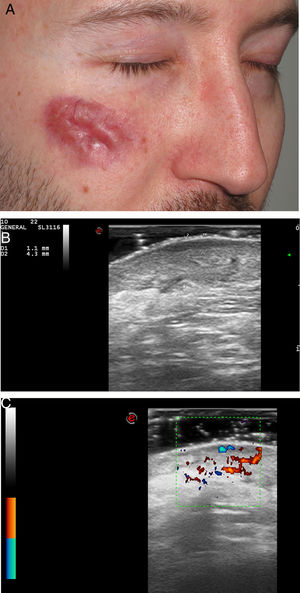

Five patients (six lesions) (four men and one woman) with a median age of 67 years (range, 39-71) and a biopsy-proven GF were included. In three of patients the lesions were located on the face, one on the scalp, one on the ear and one on the umbilicus. Most patients had undergone several treatments without clinical improvement (Table 1). On ultrasonographic evaluation, GF presented in all patients as a hypoechoic and heterogeneous lesion in dermis and hypodermis with an increased vascularity on color Doppler mode (Fig. 1–2). Almost all lesions (5/6) were ill-defined. In 5/6 GF a marked subepidermal hypoechoic/anechoic band was observed. One lesion (case 5, nose) presented a posterior enhancement. There were no significant differences in ultrasound characteristics between facial and extrafacial GF (Table 1).

| Case n | Sex/age (years) | Time of evolution (years) | Anatomic location | Previous treatments | Histological description | Ultrasound features (B-mode ) | Doppler mode |

| 1 | m/39 | 5 | right cheek | topical corticosteroids, hydroxycloroquine, dapsone, laser, topical tacrolimus | Presence of Grenz zone. Dense inflammatory infiltrate constituted mainly by eosinophils, few histiocytes, lymphocytes and occasional plasma cells. | Hypoechoic, heterogeneous and ill-defined lesion in dermis and hypodermis. | Increased vascularity |

| Subepidermal hypoechoic band | Vessels in dermis up to 0.63 mm in diameter. | ||||||